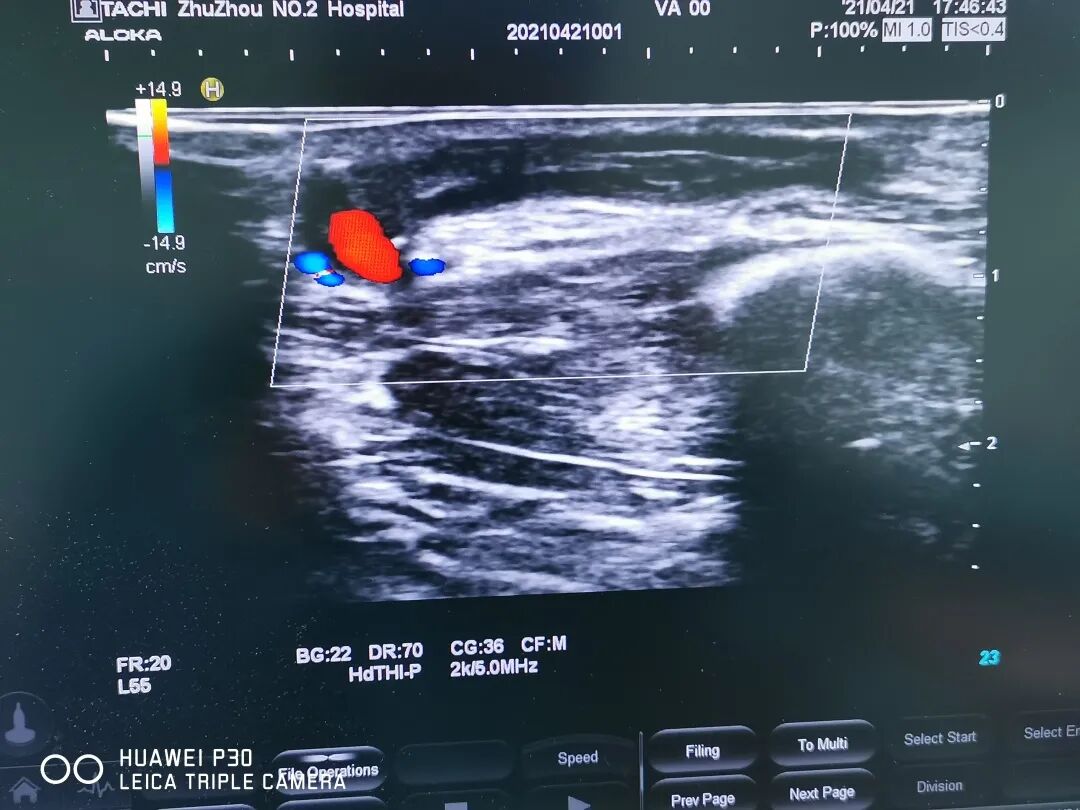

患者術(shù)后

▲球囊擴(kuò)張血彩

理解和信任往往會激發(fā)力量創(chuàng)造奇跡,在超聲科、麻醉科的通力協(xié)助下,雖然術(shù)中碰到一些問題,但都被一一解決,手術(shù)很成功,術(shù)后第二天,內(nèi)瘺穿刺上機(jī),血流量達(dá)到260ml/min,保住了寶貴的生命線,避免了置管!